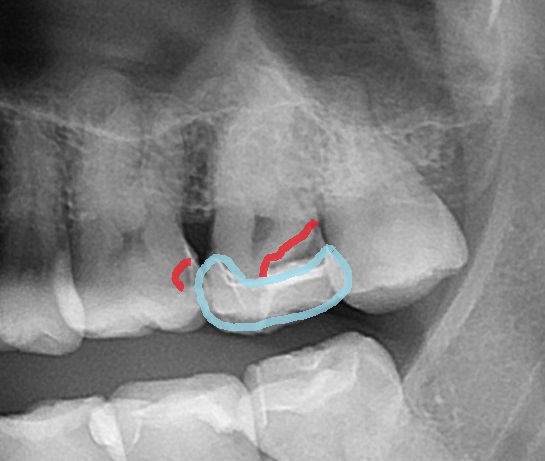

まずレントゲン写真(エックス線写真)を見てみましょう。

こちらのは歯は親知らずです(矢印)

一つ手前(左側)の歯はスケルトンのように見えますよね。

青い所がセラミックで、以前虫歯治療でセラミックを入れたようです。

赤く囲まれた所が黒く、虫歯があります。

さらに手前の歯の間も虫歯です(-_-;)

虫歯はレントゲン写真(エックス線写真)で確認ができます。

虫歯は歯が溶けてしまう病気なので、歯の内部が溶けて、

レントゲン写真で黒く写ってきます。